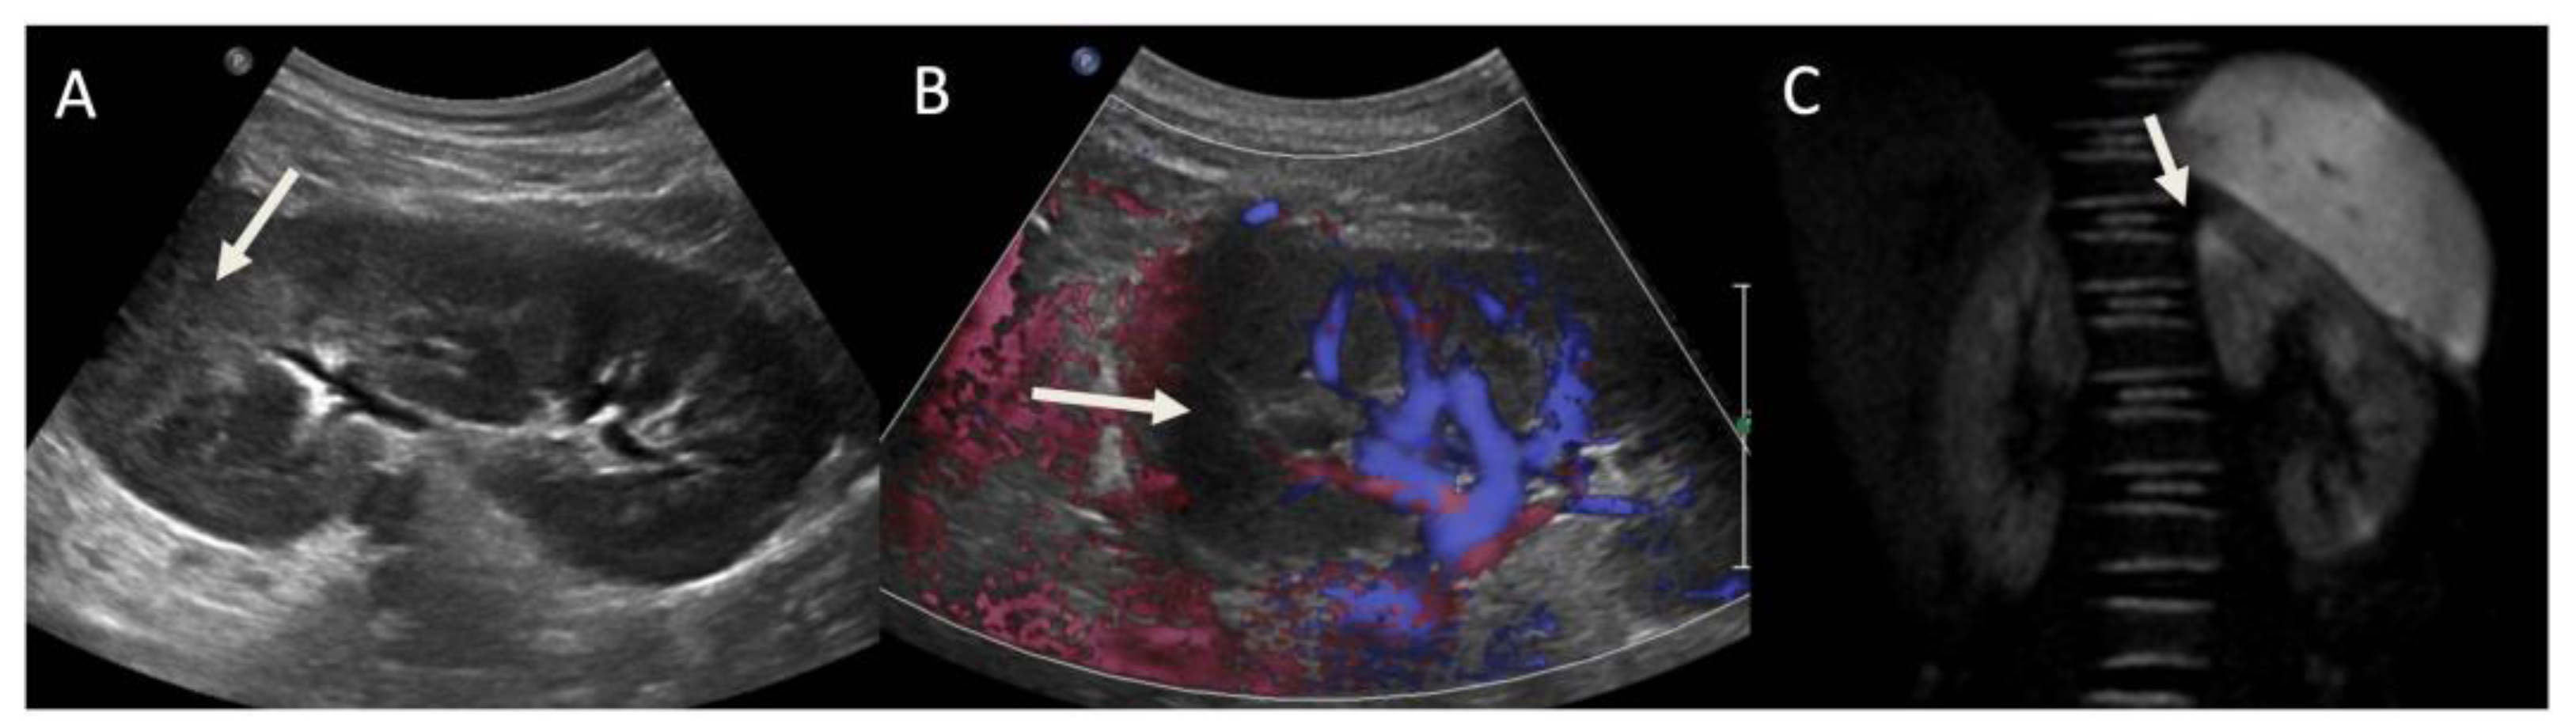

- Focal parenchymal areas with restricted diffusion;

- Seat, number, and mono- or bi-laterality of the focal renal lesions.